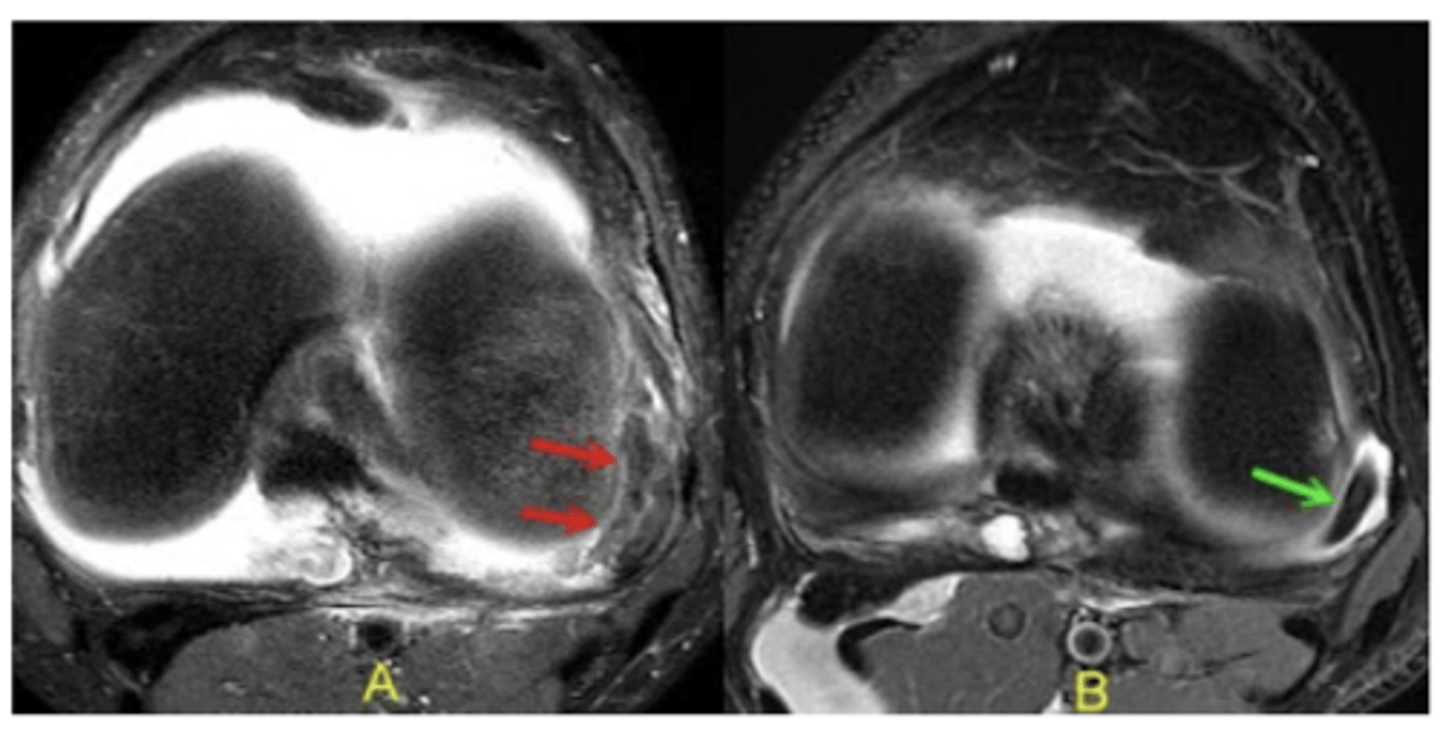

IT band-related lateral knee pain (cyst on the left image, some signal change on the right image)

Define the pathology.